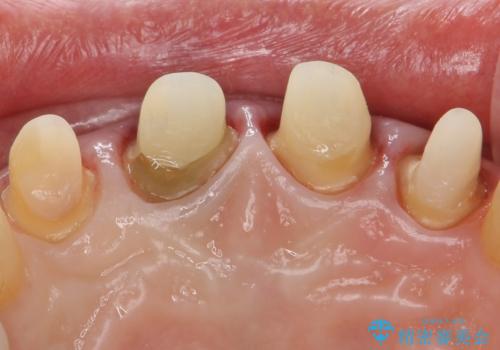

- 前歯を綺麗にしたいとのことで来院されました。

色調・適合ともに改善するために一度被せ物を外し、歯の形を整えた後に新しい被せ物を装着していきます。